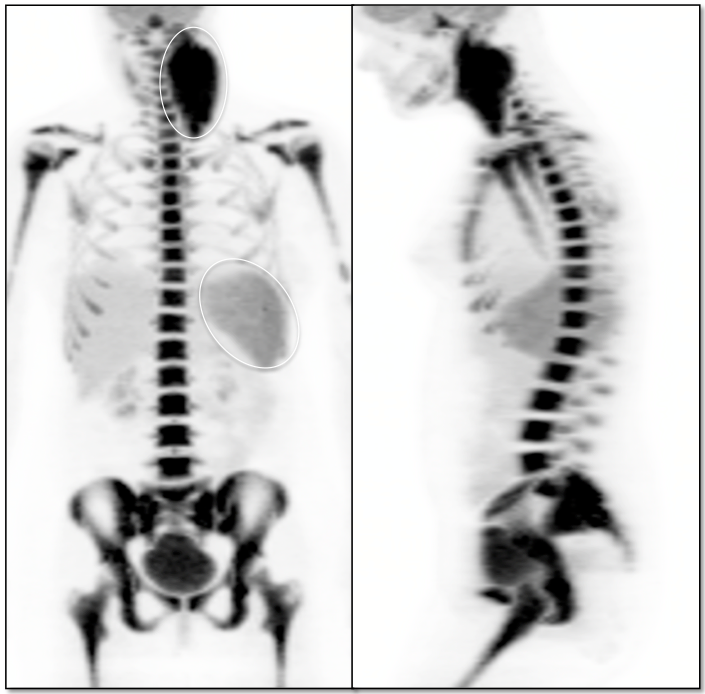

A significant percentage of patients presenting for PET/CT will have recently received chemotherapy and/or colony stimulating factors (CSF), both of which can cause significant diffuse increased metabolic activity of the spleen (and bone marrow, discussed here).

Associated splenomegaly is not uncommon.

• Before calling splenic uptake “physiologic activation”, one must confirm a history of recent chemotherapy and/or colony stimulating factors.

• The uptake must be diffuse and not accompanied by lesions on the CT images.

• If uptake is focal, or if the uptake is accompanied by identifiable lesions on the co-registered CT images, malignancy must be strongly suspected.

• As splenic activation and reactive marrow typically occur together, the presence of co-existing reactive marrow lends great confidence to the radiologist’s decision to call an enlarged and intensely avid spleen normal physiologic activation (especially in a lymphoma patient).